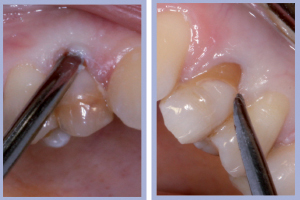

- Figg. 7a, b – Toilette chirurgica

- Figg. 8a, b – Mappatura alveolare tramite sonda parodontale

- Figg. 9a, b – Preparazione del sito di destra

- Figg. 10a, b – Preparazione del sito di sinistra